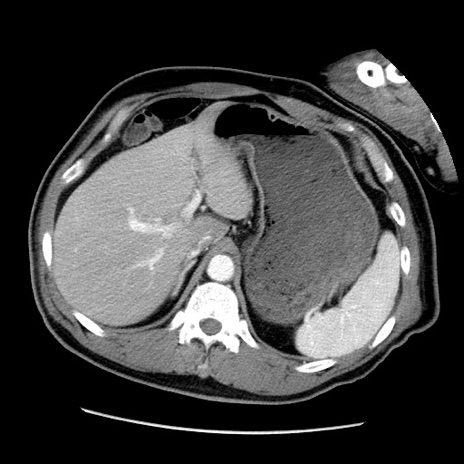

冠状断像

【症例】50歳代男性

【主訴】腹痛

【現病歴】AVMからの被殻出血のため回復期リハ病棟入院中。 本日午後3時頃急に下腹部痛が出現した。

【既往歴】AVM、被殻出血、虫垂炎、高血圧

【身体所見】意識晴明、左半身不全麻痺、会話の理解は良好、36.5°C、腹部:膨隆、全体に板状硬、下腹部正中に圧痛点あり、反跳痛-、筋性防御不明、右下腹部にope scar

【データ】WBC 9400、CRP 0.06